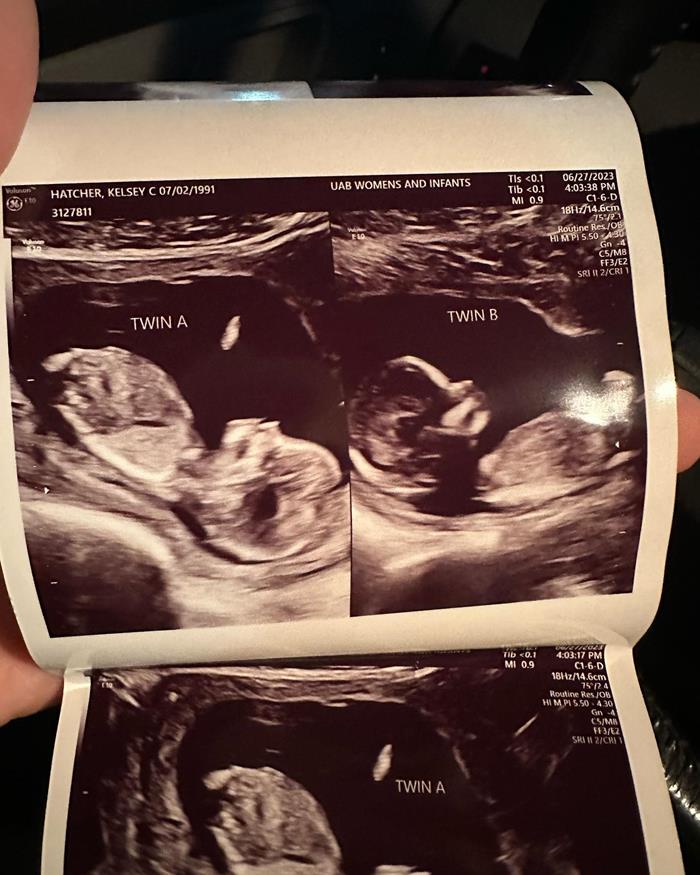

เคลซีย์เผยภาพอัลตราซาวด์ที่น่าทึ่ง แสดงให้เห็นชัดว่าเธอมีมดลูก 2 มดลูก และภายในนั้นก็มีทารก 2 คนอยู่แยกกัน โดยทั้งคู่เป็นเพศหญิง และเมื่อเร็ว ๆ นี้เธอได้ผ่านการตรวจประเมินสุขภาพของทารกในครรภ์และพบว่า ทารกทั้ง 2 ครรภ์มีสุขภาพแข็งแรง "ใบหน้าเล็ก ๆ ของพวกเขาน่ารักไหม ? คิดว่าจะคล้ายกันไหม ? ฉันรู้สึกว่าพวกเขาจะแตกต่างกันอย่างสิ้นเชิง" เคลซีย์ กล่าว